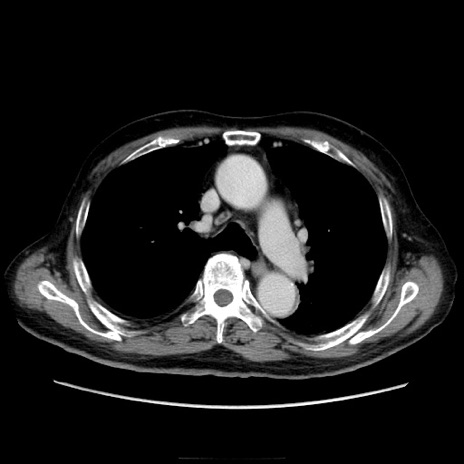

症例21(横断像)

【症例】70歳代男性

【主訴】腹痛

【現病歴】肝硬変・肝細胞癌にてかかりつけの方。約9時間前に食後より腹痛出現。症状が徐々に増悪し、嘔吐出現したため来院。

【既往歴】肝硬変、肝細胞癌(RFA、TACE後)

【身体所見】意識清明、表情苦悶様、BT 36℃、BP 129/78mmHg、P 88bpm、SpO2 97%(RA)、右上腹部から心窩部にかけて圧痛あり、反跳痛なし、筋性防御あり。

【データ】WBC 5800、CRP 0.16